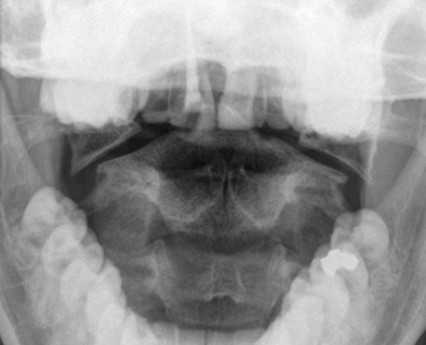

Перелом С1 Джефферсона. Рентгенография через открытый рот. С обеих сторон расширено расстояние от нижних площадок ножек С2 до боковых масс С1. Боковые массы С1 смещены латерально и перестают быть в линию с боковыми массами С1.

Обследование начинается со стандартной рентгенографии в 3 проекциях - боковой, передне-задней (прямой) и через рот.

Схема. Ход рентгеновского луча и расположение кассеты с пленкой при снимке через рот.